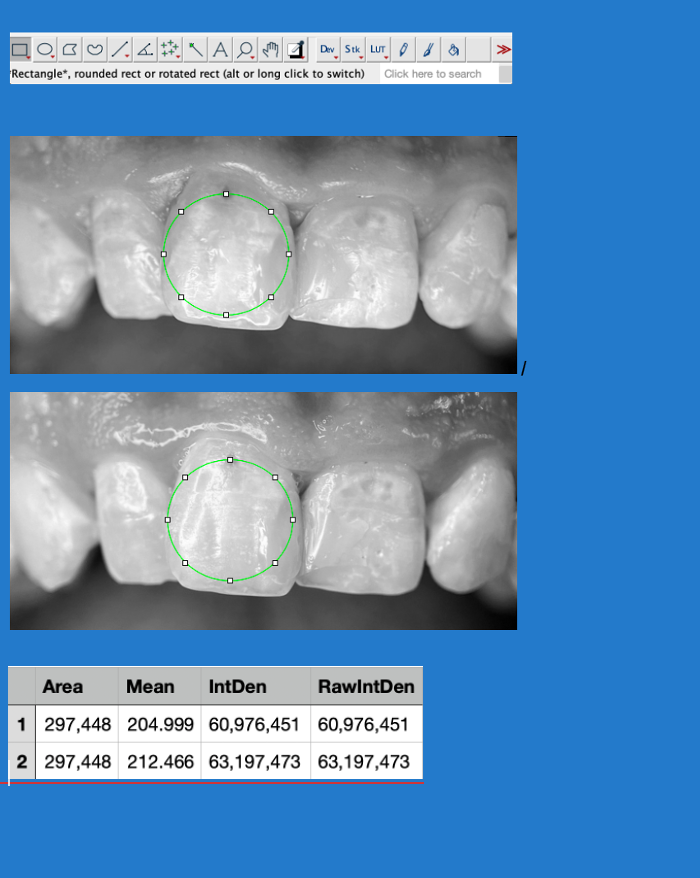

To objectively evaluate changes in enamel mineralization between baseline and follow-up images, a photometric analysis was performed using ImageJ software (version 1.54). Image acquisition was carried out under standardized conditions to ensure data comparability. To eliminate potential interference from color components, images were converted to 8-bit grayscale and subjected to brightness and contrast normalization.

For quantitative analysis, a Region of Interest (ROI) was carefully selected, ensuring that the same area was analyzed in both images for accurate comparison. As minor positional variations between images could affect the results, the TurboReg plugin was employed to perform a rigid body transformation of the follow-up image. This allowed for precise spatial alignment, enabling pixel-by-pixel comparison. Following alignment, key photometric parameters were extracted, including the Mean Gray Value (MGV), which represents the average grayscale intensity within the selected area and serves as an indicator of mineral density, and the Integrated Density (IntDen), which quantifies the total grayscale intensity across the ROI.

Results showed an increase in Mean Gray Value (+3.64%) and Integrated Density (+3.64%) in the post-treatment image, suggesting an enhancement in mineral density.

This standardized approach to photometric and image processing analysis ensures an objective and reproducible assessment of enamel mineralization. By reducing observer bias and allowing for precise pixel-based comparisons, this methodology strengthens the reliability of clinical findings and provides valuable insight into the effectiveness of remineralization treatments (Figure 3).

Figure 3.

Application of ImageJ software for photometric analysis of enamel mineralization. The selected Region of Interest (ROI), indicated by the green circle, was maintained constant between baseline and post-treatment images to ensure comparability. The white squares represent control points used to define and adjust the ROI within the software. Mean Gray Value (MGV) and Integrated Density (IntDen) were measured to quantify mineralization changes.